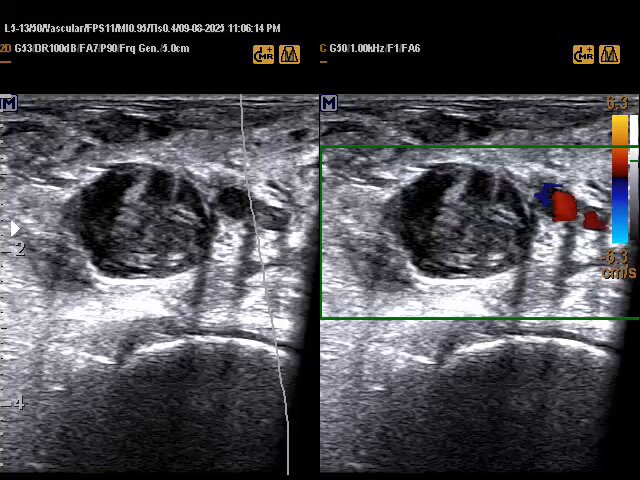

Extensive DVT and SVT in 43 years female with a history of Ovarian cancer underwent neo adjuvant chemotherapy. In such cases the operator must assess the arterial system to exclude the possibility of Phlegmasia cerulea dolens. #EchoTech